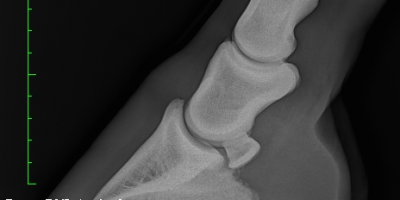

BEMVS uses the state-of-the art imaging equipment with our TruDr Lx digital xray system. This system utilises the latest technology and methods to capture the highest quality diagnostic images, with the detail far superior than conventional film x-rays. This allows x-rays to be taken on site without the need for transport to a hospital. Images … Continue reading Radiology